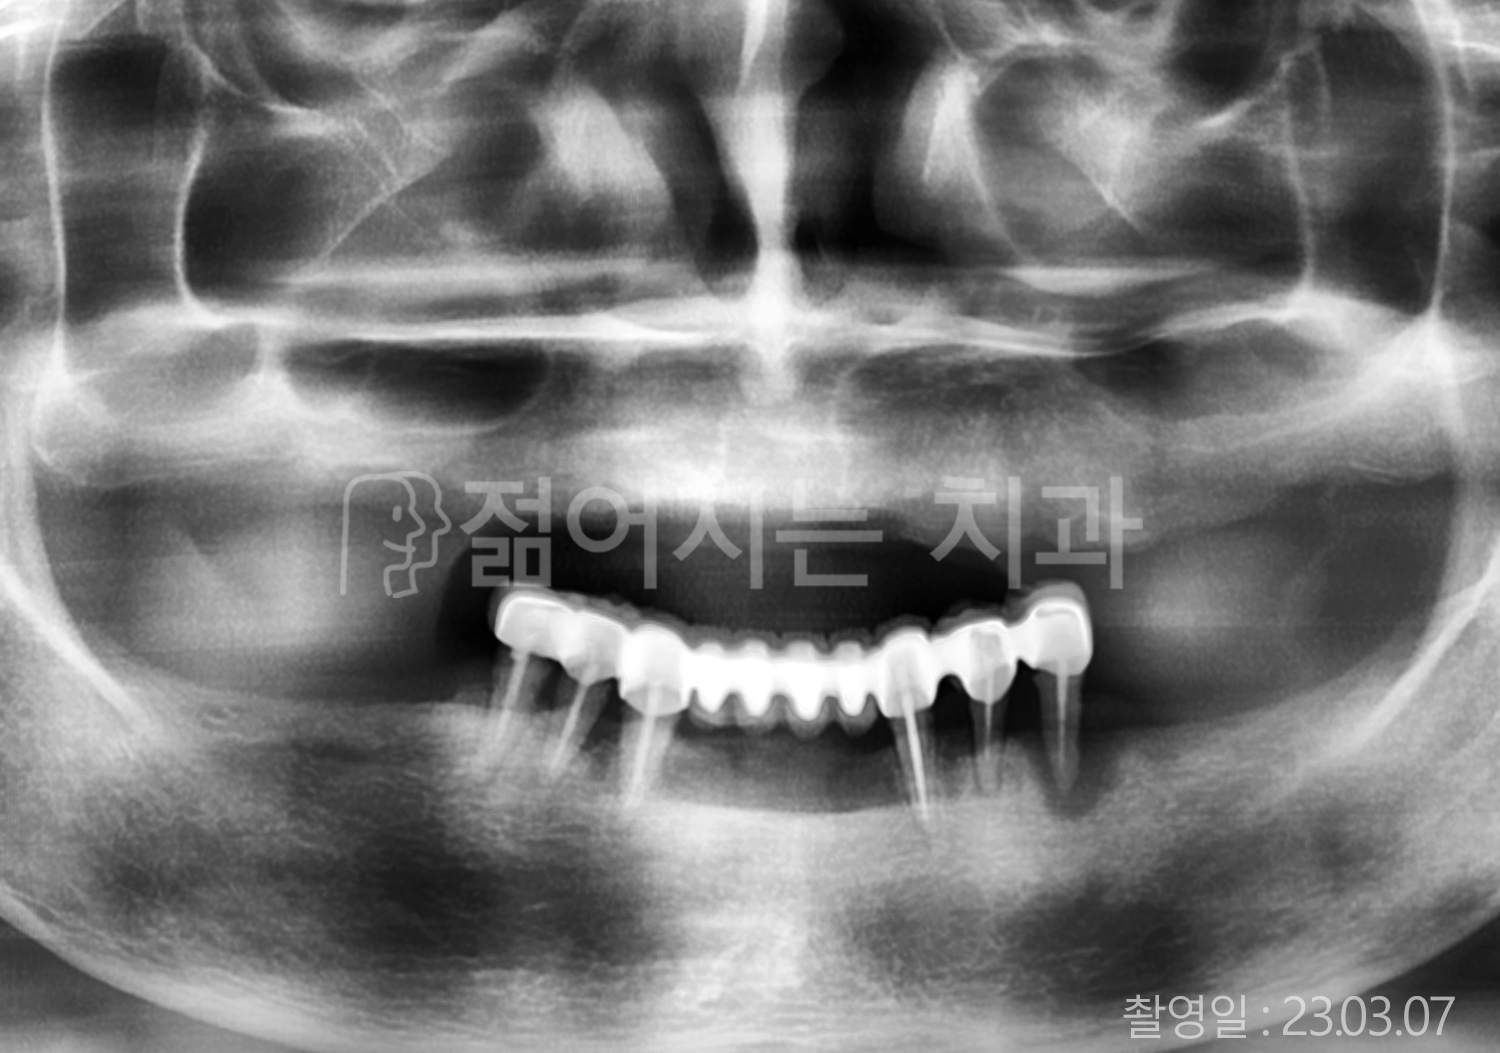

• 60대 전체치아 10개 이상 임플란트